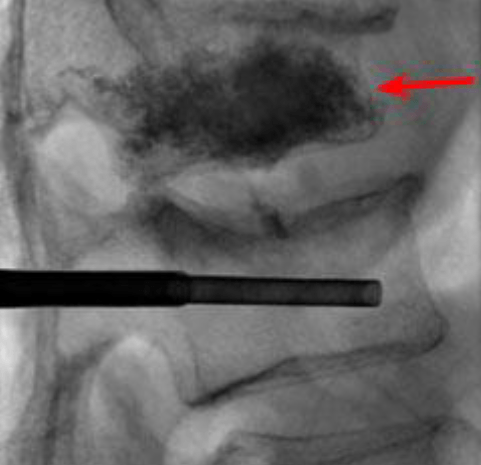

Figure 4. The balloon is removed and bone cement is injected into the cavity. Fluoroscopic x-ray shows cement in upper vertebra (red arrow) and needle inserted in lower vertebra.

Figure 2. Using fluoroscopy, the hollow needle (trocar) is inserted through the skin to a point behind the

pedicle. The needle is tapped through the pedicle into the collapsed vertebral body (viewed from above).